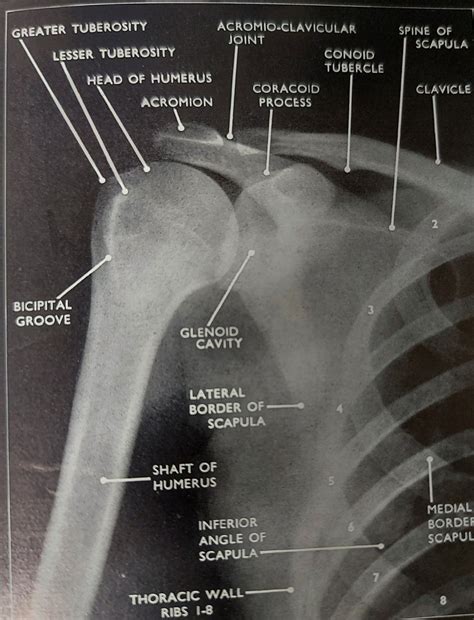

Interpreting Shoulder X Ray Views

Interpreting shoulder X-ray views requires a systematic approach to ensure that all relevant structures are assessed. Key areas to focus on include:

• The glenohumeral joint for signs of dislocation or arthritis

• The humeral head and neck for fractures or deformities

• The scapula for fractures or abnormalities

• The soft tissues for any signs of swelling or calcification

Radiologists and orthopedic surgeons use these views to identify specific pathologies and guide treatment decisions.